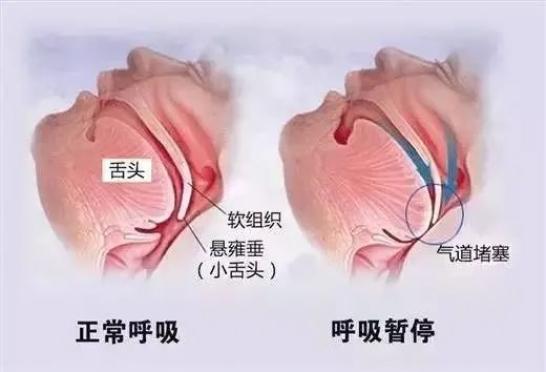

在我们进入“深度睡眠”时,全身的肌肉会放松下来,包括舌根肌肉。

如果舌根肌肉放松得太过分了,躺着时就会因为重力下垂,妨碍到呼吸道。

呼吸道里流通的空气,撞到舌根肌肉上,振动发声,就成了打呼声。

晚上睡觉一躺下,舌根肌肉一放松,就更容易妨碍呼吸道,甚至直接堵死!

晚上睡觉一躺下,舌根肌肉一放松,就更容易妨碍呼吸道,甚至直接堵死! 这种情况,叫“病理性打呼”。